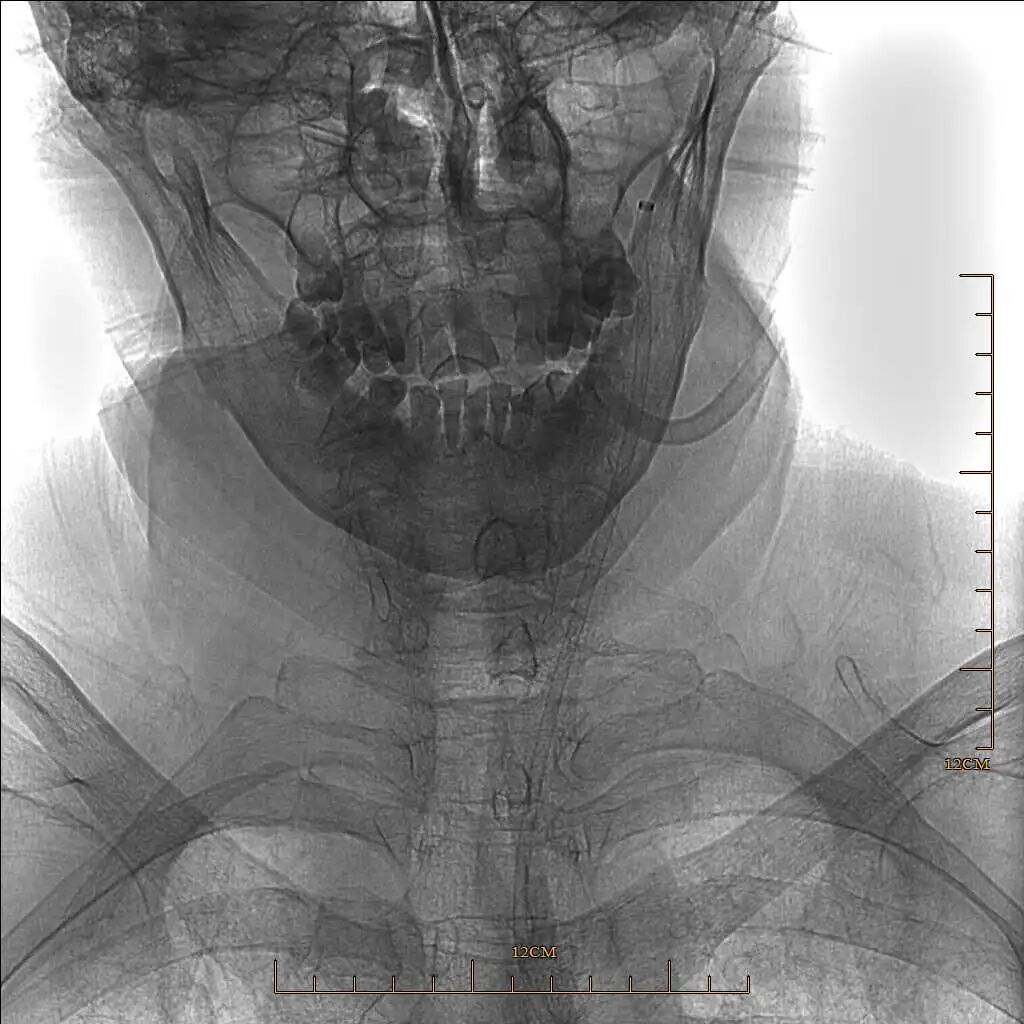

术前影像学检查结果

术前CTA提示左侧大脑中动脉M1段闭塞。

90cm Locaste 088输送导管建立路径,造影提示左侧大脑中动脉M1段闭塞。